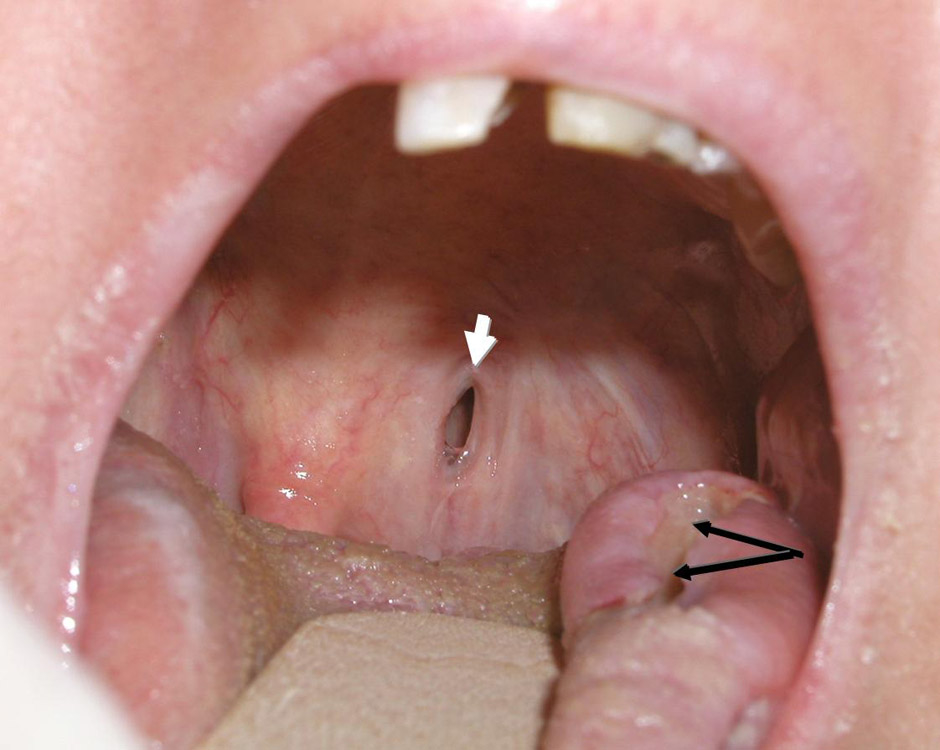

Figure 3

Lateral tongue ulceration (black arrows) and palatal fistula (white arrow) in a patient with GPA.

Tongue or gum ulcerations are not infrequent in GPA (fig. 3), as is gum sensitivity or hypertrophic strawberry-like gingivitis [38]. In addition to lingual ulcerations, infarction of the tongue has been reported.